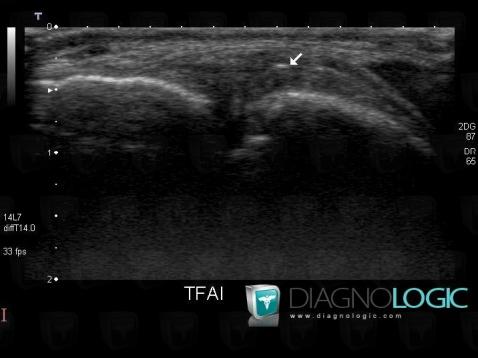

Other ligament injury / Ankle, Other ligaments - Ankle, US

Here is the specific information in the key image above:

- Diagnosis Other ligament injury / Ankle, Location(s) Other ligaments - Ankle, with gamuts Ankle ligament injury